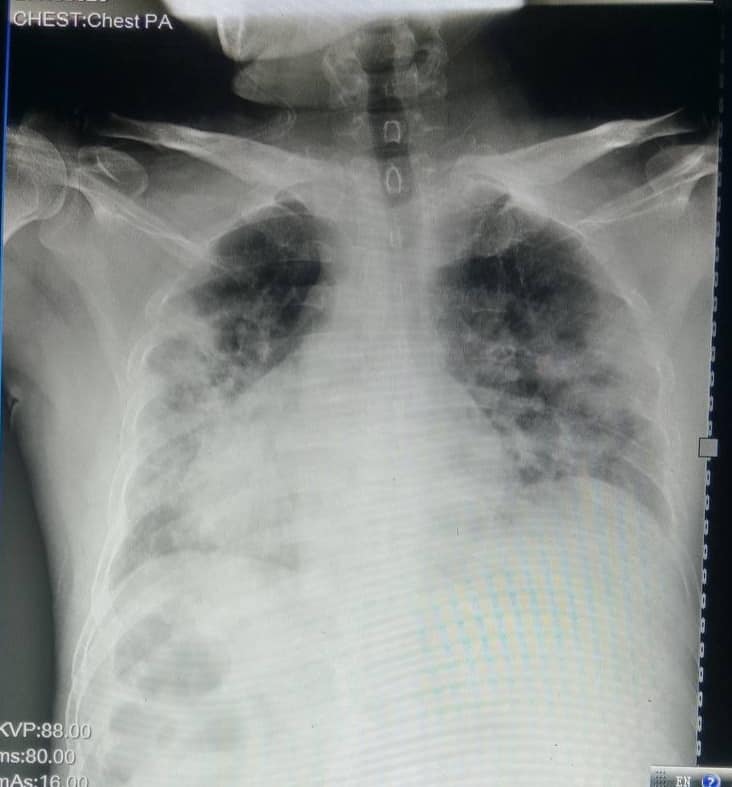

“មានបទពិសោធន៍ជាង1ឆ្នាំក្នុងគ្រប់គ្រង និងព្យាបាលជំងឺកូវីដដោយគ្មានការភ័យខ្លាចឬតក់ស្លុតឡើយ ។ តែក្នុង1ខែចុងក្រោយនេះចាប់ពី 20 កុម្ភៈ 2021 ខ្ញុំមានអារម្មណ៍ភ័យខ្លាច និងព្រួយបារម្ភណាស់ ពីព្រោះវាជាប្រភេទមេរោគប្រែរូបថ្មី (variant virus strain) ដែលក្នុងរយៈពេលតែ2ទៅ5ថ្ងៃវាវាយលុកចូលសួតធ្វើអោយរលាកធ្ងន់ធ្ងរទាំងសងខាង ។ រូបភាពសួតត្រូវបានមេរោគស៊ីសុះសាច់ដ៏គួអោយខ្លាច ។